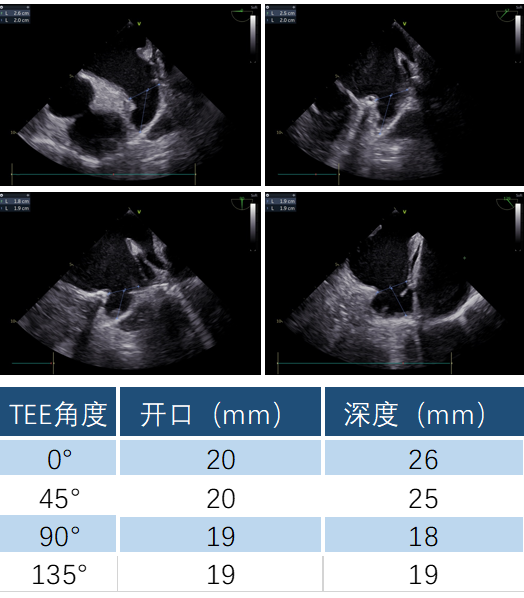

TAVR手术完成后,在TEE指导下,白明教授顺利偏下偏后完成了房间隔穿刺,同时TEE再次检查左心耳开口19-20mm。DSA造影观察与术前CTA多平面重建结果吻合,左心耳浅鸡翅型,测量左心耳开口24.9mm深度22mm。经过充分讨论和手术策略分析,决定为患者使用WATCHMAN FLX™ 31mm封堵器进行左心耳封堵。WATCHMAN FLX™器械由于和WATCHMAN设计的不同,导引鞘不需要进入左心耳远端,即可安全展开封堵器。术中白明教授送入WATCHAMN FLX™ 31mm输送系统后,退鞘形成FLX BALL,后采用进退结合法,“毛毛虫”式展开封堵器。造影观察封堵效果理想,牵拉试验稳定,在TEE上观察封堵器微露肩,压缩比21%,各角度无残余分流,最终释放左心耳封堵器。术后观察患者心包积液相比术前无变化,生命体征平稳,一站式手术顺利完成。

术中TEE各角度检查左心耳